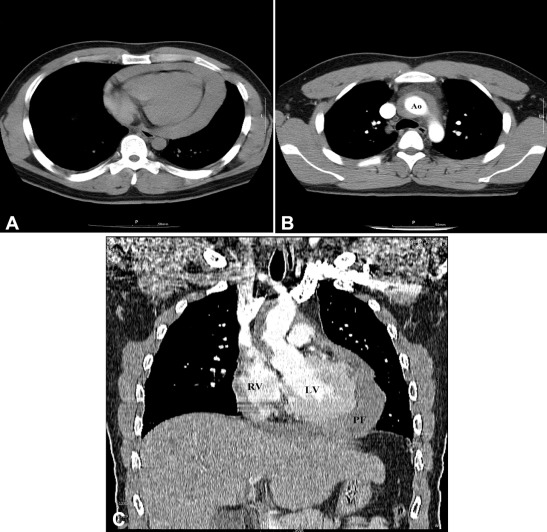

A 26-year-old man was who transferred to our hospital was diagnosed to have aortic IMH with cardiac tamponade. On admission, the patient showed confused mentality and heavy sweating. His initial vital signs were as follows: systolic blood pressure, 60–70 mmHg; heart rate, 130–140 beats/minute; peripheral oxygen saturation, 70–75%. The jugular vein was engorged, but hepatomegaly or audible cardiac murmurs were not detected. A chest X-ray showed cardiomegaly with a cardiothoracic ratio of 58%. An electrocardiogram (ECG) showed sinus tachycardia with a heart rate of 128 beats/minute and T abnormality of inferior leads. A chest CT scan previously taken from another hospital revealed IMH and pericardial effusion without any evidence of abnormal mass in chest structure (Fig. 1).

Chest computed tomography findings. (A) Unenhanced scan shows large pericardial ...

Figure 1.

Chest computed tomography findings. (A) Unenhanced scan shows large pericardial fluid collection with computed tomography density measurements consistent with hemopericardium. (B) Enhanced axial scan shows aortic intramural hematoma without any evidence of abnormal mass in chest structure. (C) Enhanced coronal view shows large pericardial fluid collection and aortic intramural hematoma. Ao = aorta; LV = left ventricle; PF = pericardial fluid; RV = right ventricle.